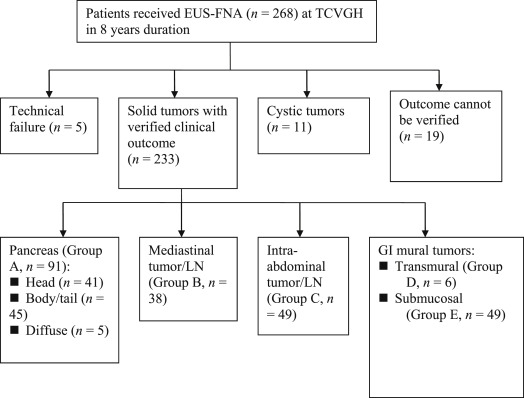

Among the 268 patients, 233 patients with successful FNA procedures for solid tumors (98 women, 135 men) with verified clinical outcome for review were included in this study. These patients were classified according to the anatomic location of the lesions as pancreatic tumors (Group A, n = 91), mediastinal tumors (including lymph node) (Group B, n = 38), abdominal tumorous lesions (including lymph node) (Group C, n = 49), focal transmural thickening of the GI tract (Group D, n = 6, all were with nonspecific diagnosis from endoscopic biopsy), submucosal tumors of the GI tract (Group E, n = 49) ( Table 1 ; Fig. 2 ). The accuracies of pathological diagnosis of malignancy were 79.2%, 76.9%, 93.2%, and 80% for groups A–D, respectively. The respective sensitivity, specificity, PPV, NPV are also shown (Table 2 ). The respective proportion of the pancreatic tumors according to the different locations and their diagnostic accuracies are shown in Fig. 3 . In total, for all of these lesions, the overall accuracy for the diagnosis of malignancy was 82.9%. For the stromal tumors of the GI tract in Group E (all originating from below the submucosal layer), FNA cytopathology showed evidence of specific diagnosis of GIST in all (47%) of these cases, 14% were diagnosed as suspicious (most were of a spindle cell tumor nature, except for one adenocarcinoma) and 39% were considered negative for tumor or non-diagnostic. For the patients with negative or non-diagnostic FNA cytopathology, none were found to have an outcome of malignancy progression or tumor-related morbidity/mortality (Fig. 3 ).

Figure 2. Patient recruitment and classification according to anatomical characteristics of the lesions. |